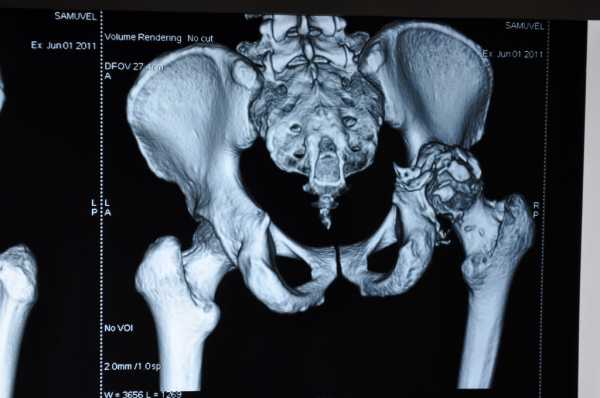

Снимок компьютерной томографии перелома таза в области вертлужной впадиныДля того чтобы быть полностью уверенным в диагнозе, врач также назначает пройти диагностирование на компьютерной томографии. Благодаря такому методу диагностирования можно точно обнаружить смещение или присутствие оскольчатого перелома. Для определения открытого перелома проводится ректальное и вагинальное обследование.

- трехпроекционная рентгенография таза и самого сустава;

- компьютерная томография.

Компьютерная томография таза

Данные исследования позволяют установить какой именно участок вертлужной впадины был разрушен, есть ли смещение костей. С целью оценить неврологическую составляющую для консультации приглашается невропатолог. На основе собранных данных врач формирует диагноз и определяет тип перелома.

Ставят диагноз основываясь на симптомах, данных рентгенологического и КТ исследований. Рентген делают в нескольких проекциях, снимок в прямой проекции оказывается малоинформативным для установления характера полученных повреждений.

КТ проводят для постановки более точного, правильного диагноза. Она позволяет определить наличие или отсутствие смещения костных фрагментов. Ректальным и вагинальным методами исследования определяют характер перелома, он может быть открытым или закрытым.